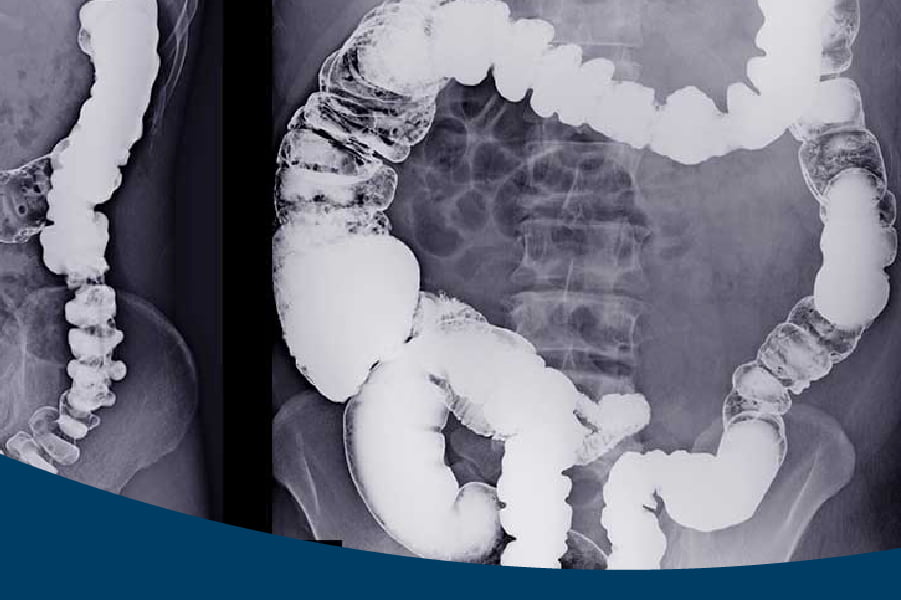

Bário: este é dado para o paciente ingerir via oral e é utilizado pelos exames de raio-x e tomografia, com o objetivo de analisar os órgãos do sistema digestivo como esôfago, intestino e estômago.

Iodo: essa substância pode ser aplicada no paciente via oral, com o objetivo de verificar o sistema digestivo, como também via venosa, ou seja, na veia, para avaliação de variadas lesões, inflamatórias, infecciosas e/ou tumorais.Também é utilizado pelo raio-x e pela tomografia.

- Estudo radiológico do trato gastrointestinal.